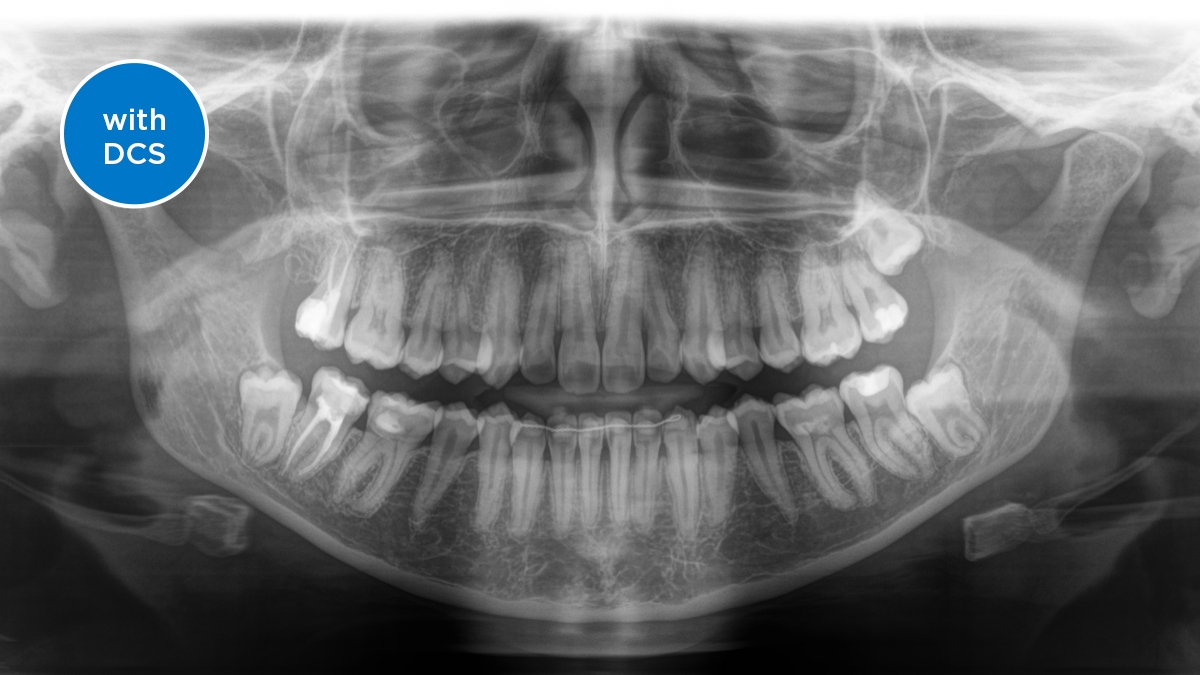

We developed a 10-point concept for easy patient positioning and X-ray imaging. Our concept is primarily about two things: high image quality and comfort for the patient and the assistant. This concept supports and provides the tools needed to ensure high-quality images for treatment analysis and focuses on ergonomics and comfort for the patient and assistant.